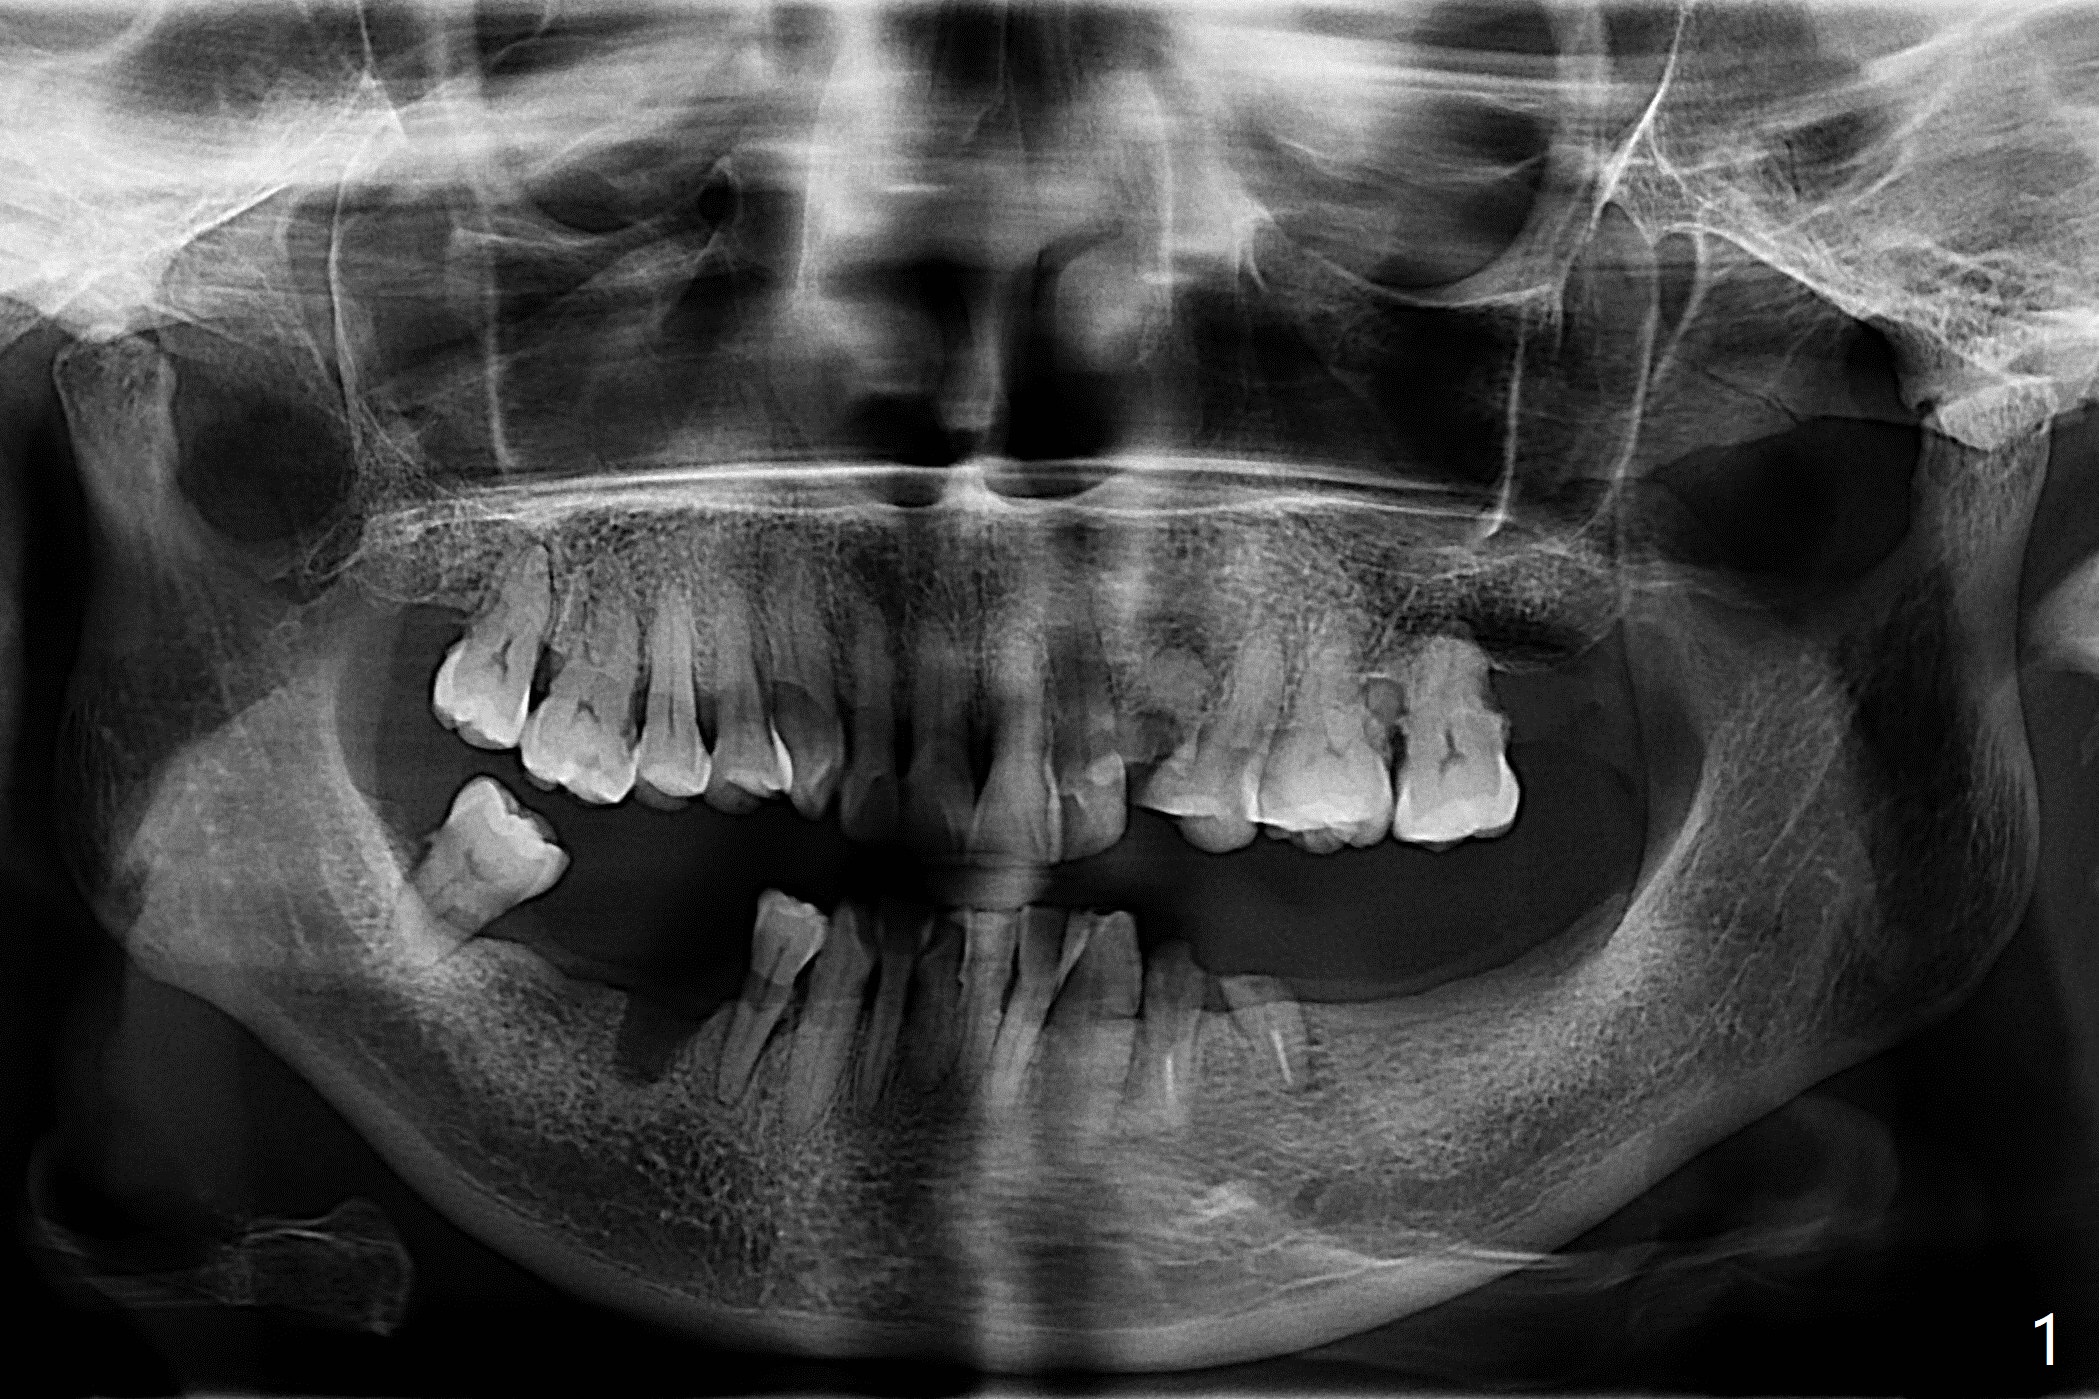

A 61-year-old woman with small statue, partial edentulism and bite collapse (deep bite) (Fig.1) requests an implant at #11 first (Fig.2). A 4x17 mm tissue-level implant is planned.